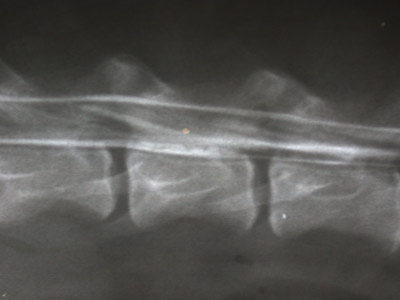

Myelographie des Rückenmarkkanals Hund hatte eine entzündliche Erkrankung

des Rückenmarks und keinen Vorfall der Bandscheibe wie erst vermutet

Die Kontrastmittelsäule fliesst ungehindert bis zum Schwanzwirbel